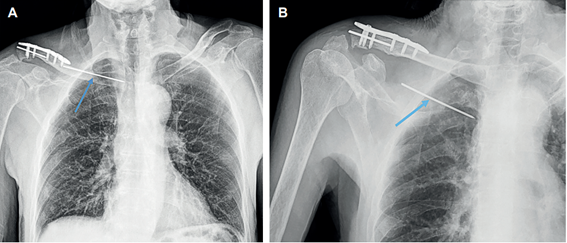

Un mes después consultó por presentar dolor severo en hombro derecho y dificultad respiratoria de dos días de evolución. En la radiografía de hombro derecho se observó migración de uno de los clavos de Kirschner, ubicado en el aspecto superior del hemitórax ipsilateral (Figura 3). Se solicitó una angiotomografía de tórax que evidenció un cuerpo extraño ubicado en la región infraclavicular, que correspondía al clavo de Kirschner intratorácico, y el extremo distal en contacto con el parénquima pulmonar del segmento apical del lóbulo superior derecho. No presentaba neumotórax, focos neumónicos ni lesión vascular (Figura 4). Los laboratorios no mostraron leucocitosis, ni neutrofilía, por lo cual no requirió antibioticoterapia.